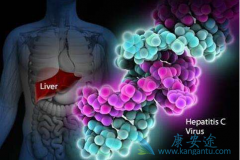

看过那么多丙肝病毒感染暴发引起的悲剧之后,我们不得不静下心来重新审视我们的罪魁祸首,对于一名四处流窜的“惯犯”,了解他的作案动机,摸清他常用的作案手段,对于防止他再犯有重要的意义。丙型肝炎病毒(HCV),病毒体呈球形,直径小于80nm,为单股正 ...

丙肝前期没有明显的症状,很多人都会忽略它,甚至有人发现之后,认为它对身体的损害较小,所以也没有进行及时治疗,那么 丙肝需要治疗吗 ?当然是需要的。慢性丙肝可引起严重的肝损伤,包括肝硬化或肝脏瘢痕。丙肝不仅对肝脏产生很大的危害,不及时治疗 ...

丙肝同乙肝一样,是一种常见的肝脏疾病,它的危害性已经为人们所知晓了,它不仅会损害患者的身体健康,而且还具有很强的传染性,会给家人和朋友等带来潜在的威胁。而我们知道,在检查丙肝的时候是需要做肝功能检查的,有时候在做这项检查的时候发现肝功 ...

丙肝的发病比率约为3.2%,根据最新估算,世界上有超过1.85亿人感染丙肝病毒,而在中国至少有4000万丙肝患者,也就是说100人里面至少有3人患有丙肝,而绝大部分人还不知道自己已经被 丙肝病毒 感染了。丙肝具有极强的隐蔽性,初期症状并不明显,但是丙肝 ...